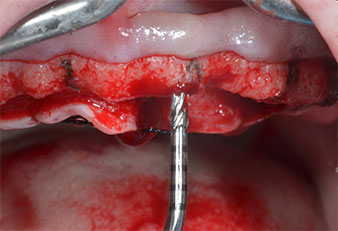

Un insert piézoélectrique diamanté de forme effilée (Piezomed I1) a été utilisé pour marquer les positions implantaires et effectuer la préparation pilote (Fig. 3). On a pris soin de travailler selon un mouvement ascendant et descendant, à puissance réduite, irrigation complète et basse pression (moins de 300g). Ensuite, un insert pilote (Piezomed I2A/I2P) a été utilisé pour l’agrandissement initial de 2mm du diamètre des sites implantaires (Fig. 4), suivi d’un insert de 3mm (Fig. 5).

Dans le cas présent, les inserts Z25P et Z35P n’ont pas été utilisés car l’os postérieur était relativement mou

et l’intervention sur celui-ci a été aisée avec le I3A/I3P.

Compte tenu de la dureté relative de l’os (D2) à cet endroit, les sites recevant des implants de 10mm de long aux régions 11 et 21 ont été finalisés à l'aide d’une fraise de 4mm de diamètre, associée à un contre-angle chirurgical W&H WS-75 L, au moteur d'implantologie Implantmed de W&H ainsi qu’au module Osstell ISQ de W&H. En revanche, en raison de leur structure osseuse molle, les sites postérieurs ont été préparés en vue de l’obtention d’un diamètre final de 3mm à l'aide de l’insert Piezomed I3P. Les implants ont enfin été posés par voie transgingivale (Flap Less) pour obtenir l’ostéointégration dans un délai de trois mois (Figures 6-10). L'appareil existant a été maintenu sur quatre implants provisoires (Fig. 8).